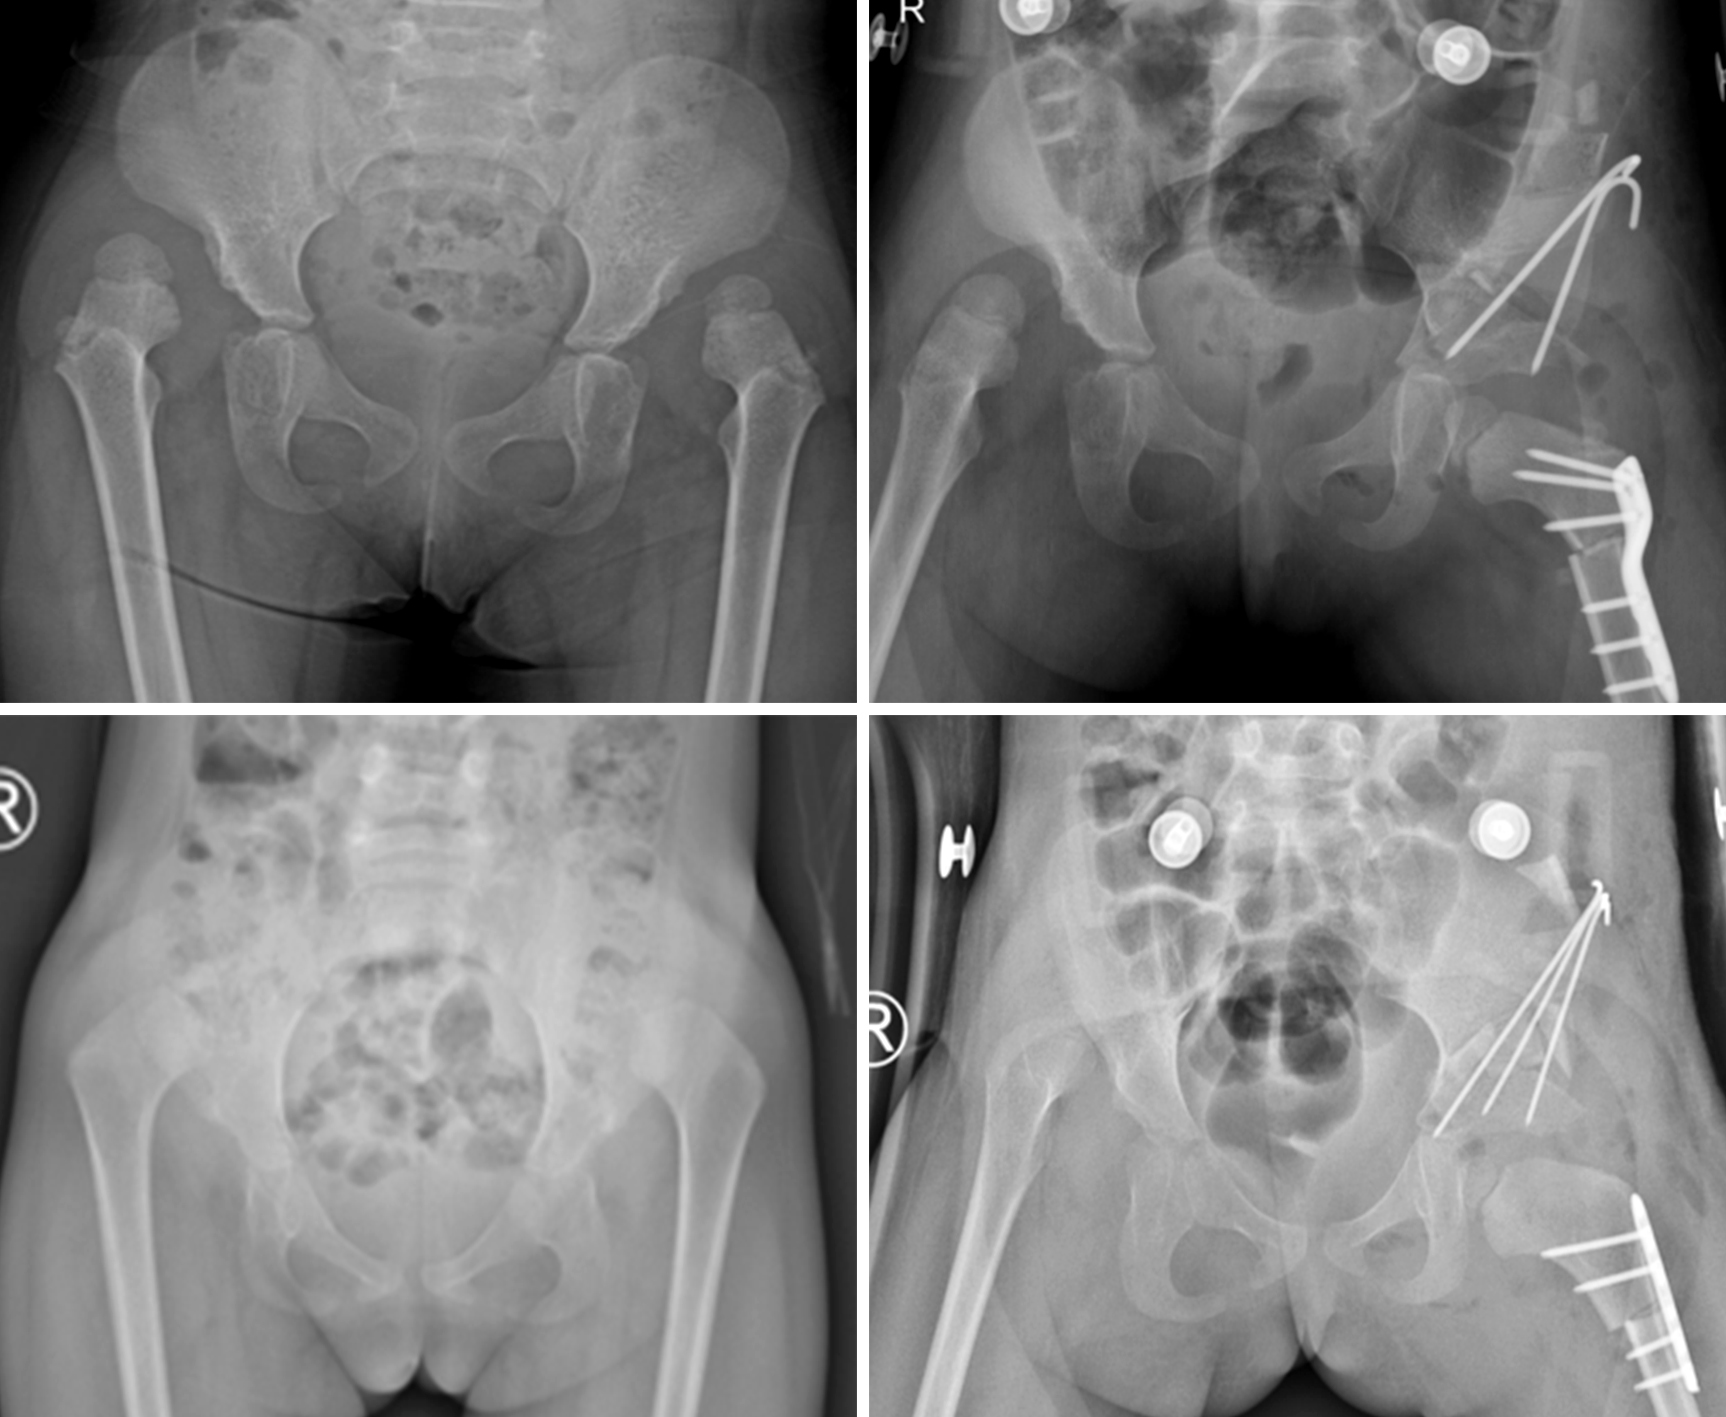

两例患儿分别为2岁11月、3岁8月,均因行走步态异常诊断为“双侧发育性髋关节脱位”。入院后进一步完善临床查体和相关辅助检查,详细测量相关数据,因患儿发育性髋关节脱位病理改变严重,髋臼指数大、髋臼浅,常规的截骨手术难以达到良好的矫形效果,经讨论评估后,决定由小儿骨科副主任医师任小军团队为患儿实施髋关节开放复位、改良微创骨盆截骨术,同时联合股骨短缩去旋转截骨术。根据术前测量数据,术中精确调整患儿髋臼指数、外侧中心边缘角、前侧中心边缘角、前倾角等指标,骨盆截骨采用有限显露髂骨内侧、髂骨外侧不用显露的基础上施行改良“L”形微创截骨,截骨线起自髂前下棘下方、终于髋臼“Y”形软骨偏后方,较传统Pemberton截骨术式“X”线透视较少,用时省,且创伤更小,术后髋关节活动范围好并达到良好的同心圆复位,术中出血少,术后患儿恢复良好,术后1周康复出院。